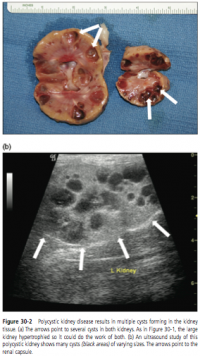

Polycystic Kidney Disease